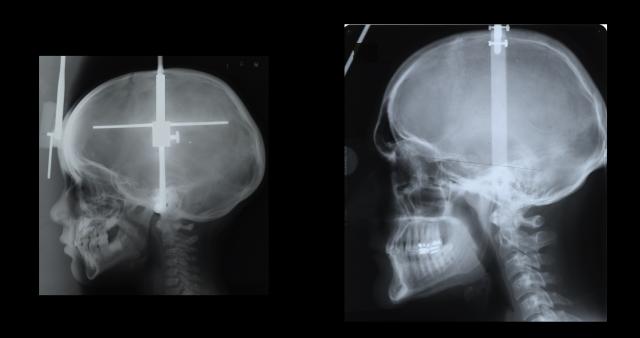

Using advanced facial and cranial biomechanical analyses with nearly 40 people whose measurements were plotted from toddlers to adults, the UI team concludes mechanical forces, including chewing, appear incapable of producing the resistance needed for new bone to be created in the lower mandible, or jaw area. Rather, they write in a paper published online in the Journal of Anatomy , it appears the chin's emergence in modern humans arose from simple geometry: As our faces became smaller in our evolution from archaic humans to today--in fact, our faces are roughly 15 percent shorter than Neanderthals'--the chin became a bony prominence, the adapted, pointy emblem at the bottom of our face.

The researchers examined how the jaw region generally reacted to two forces--vertical bending and wishboning. In wishboning, one side of the jaw is pulled outward, resulting in compression in the outer part of the chin. In vertical bending, the ramus--the posterior more or less vertical part on each side of the lower jaw--splays outward, tensing the chin area. In both instances, the thinking went, the chin area is being mechanically stressed; on a microscopic level, new bone is being created, much like lifting weights creates little tears that allows new muscle to be created. Thus, arose the theory that mechanical forces, such as chewing, led to our chins.

But in examinations from periodic measurements of participants' heads from 3 years of age to more than 20 years old, the UI researchers found no evidence that these imperceptible mechanical forces led to new bone in the chin region. Instead, they found nearly the opposite: Individuals with the most mechanical resistance had chins most similar to a 3 -or 4-year-old--meaning they didn't have much of a chin at all.